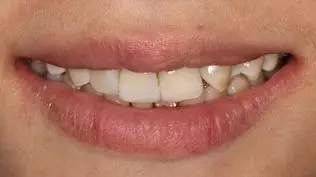

術(shù)后微笑照

術(shù)后1 周復(fù)診

主訴:11,12,21,23復(fù)診訴無不適。

口內(nèi)檢查:11,12,21,23 充填體完整,充填體周緣顏色正常,叩(-),冷熱刺激無明顯不適,無明顯松動 ,口腔衛(wèi)生尚可,牙齦正常。

處理:使用Super- Snap拋光系統(tǒng)對11,12,21,23進(jìn)行再次拋光。